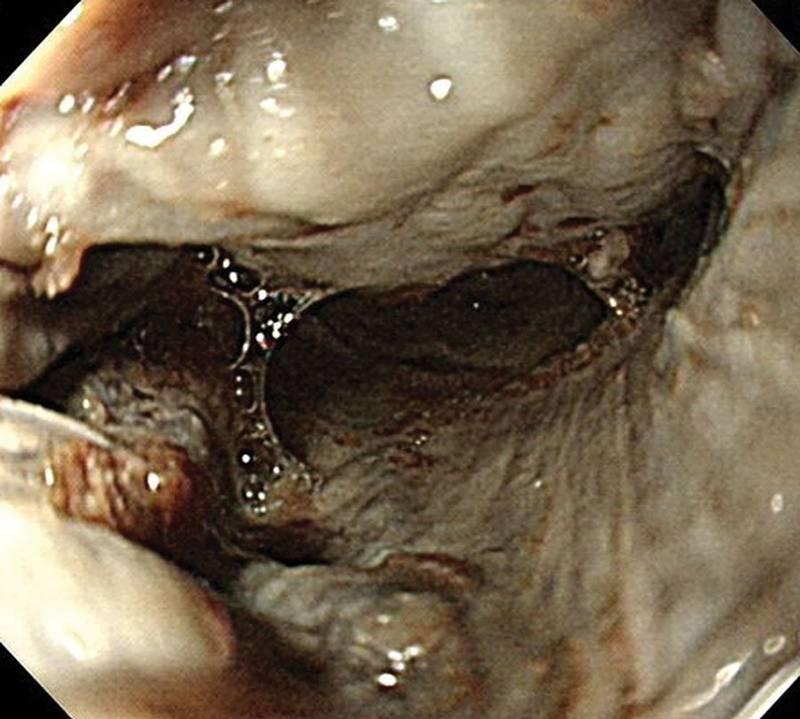

体检显示口腔糜烂,腹部弥漫性压痛,腹膜体征阳性。此外,在插入Foley导管后,观察到深色、带血的尿液(图1);肌酐水平为1.1mg/dL,血清钾为5.1meq/L,尿液分析显示每个高倍视野有38个红细胞和2个白细胞。初始动脉血气分析显示代谢性酸中毒(pH 7.130,pCO2 23 mm Hg,pO2 140 mm Hg,HCO3 8 mmol/L,碱剩余-19.8 mmol/L,SaO2 98.3%);施用440mL 7%碳酸氢钠。计算机断层扫描显示食管壁水肿,表明腐蚀性食管损伤,右下叶磨玻璃影,双侧下叶局灶性实变。观察到左侧胸腔积液和腹水。

图1 观察到急性肾小管坏死引起的深色血尿

在病例中,尿液呈深色表示肉眼血尿,提示急性肾损伤或急性肾小管坏死。这种情况可能是由于休克和循环血容量减少引起的局部缺血引起。或者,从受损的食管和胃黏膜吸收的肾小管梗阻副产物,特别是血红蛋白,可能会导致肾功能障碍。因此,急性肾功能衰竭是内镜3级粘膜损伤患者的另一个危险因素,尽管没有穿孔,但仍需要紧急干预。